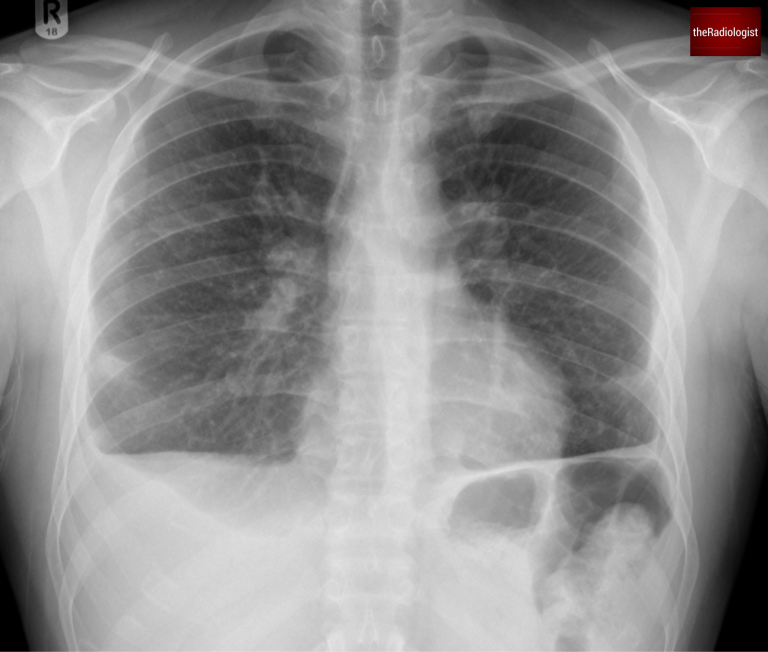

After several weeks of treatment, including chest drains, the patient improved. A follow-up chest X-ray showed almost complete resolution of the lung opacities and pleural effusions.

A follow up chest X-Ray shows almost complete resolution of the right lung nodules.